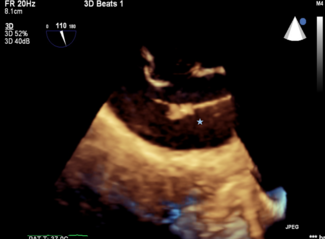

The authors report the case of an 88-year-old woman with paroxysmal atrial fibrillation, sick sinus syndrome status post-permanent dual chamber pacemaker, elevated thromboembolic risk, severe aortic stenosis, and a history of bleeding that...